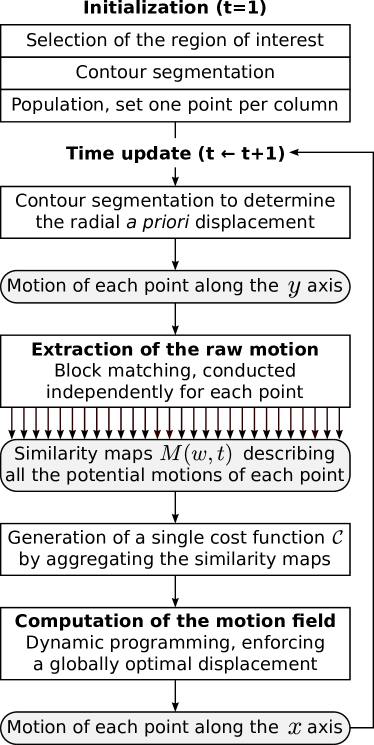

The method introduced here is devised to simultaneously extract the motion of all the points located on a line. The main steps of the method—hereafter referred to as Dynamic Block Matching (DBM)—are illustrated in Figure 2. The framework is composed of two principal operations: First, a block matching search is conducted independently for all the assessed points, then the resulting similarity maps are exploited in the context of a dynamic programming scheme to determine the global optimal displacement map of the ensemble of points. The remainder of this section is organized as follow: First the image acquisition procedure is defined, then the DBM framework is presented in detail, next the evaluation protocol is described, finally a quantitative analysis between LOKI-derived parameters and cardiovascular risk factors is proposed.

II.2.1 Initialization

First, a ROI is determined by manually indicating the left and right borders of the full exploitable width of the far wall in order to clip out noisy regions (Figure 3a). All the subsequent steps of the framework are fully-automatic.

In each frame of the image cine-loop, the contours of the lumen-intima (LI) and media-adventitia (MA) interfaces are segmented within the ROI (Figure 3a), using a previously validated method zahnd2017fully . Briefly, the contour segmentation framework is based on a front propagation approach specifically devised to simultaneously (as opposed to one after the other) extract the two anatomical interfaces of the intima-media complex. This is achieved by building a 3D space (LI depth MA depth width), where the minimum-cost path is a medial axis that describes, in each column of the image, i) the center of the intima-media complex, and ii) its thickness. The LI and MA contours can immediately be deduced from the medial axis.

In preparation for a block matching scheme, the contour information is used to populate a mesh of points , with and , in the first frame of the cine-loop. One point is placed in each column of the ROI, in the center of the intima-media complex (Figure 3b,e).

II.2.2 Extraction of the raw motion

This operation consists in estimating the motion field , namely the relative -wise displacement of each point in each frame of the cine-loop. This process being carried out independently for each point, the description of the operation will be given for a single point at a given time step. The previously described interpolation scheme is applied to the frames and . A block matching operation is then carried out between these two consecutive frames: a rectangular block of size is centered around in the frame, and a search window of size is explored in the frame. Matching similarity is evaluated with the sum of squared differences (SSD) metric.

Let us briefly recall three specificities that are most generally followed by traditional block matching approaches: i) the next position of the tracked point is blindly determined by the coordinates of the global minimum in the SSD map, ii) the search window in the frame is centered around , and iii) the reference block corresponds to the speckle pattern centered around the currently tracked point . In comparison with traditional implementations, these three specific points are addressed differently by the present framework, as described hereafter.

First, the search is guided along the direction using a previously validated contour segmentation method zahnd2017fully . The rationale is to perform a first estimate of the wall radial displacement to guide motion tracking and systematically ensure that the tracked points remain within the intima-media complex. Guidance is realized by automatically setting the coordinate of the center of the search window in the center of the intima-media complex in the frame (Figure 3c). The segmentation method has been reported to delineate the LI and MA interfaces with a mean absolute error () of and , respectively zahnd2017fully . Therefore, block matching is conducted along the direction with a reduced maximum displacement , in order to allow a fine search around the initial position provided by contour segmentation. In contrast, since no a priori guidance is provided along the direction, a wider exploration range is permitted, with . This value has been selected based on the maximum expected displacement between two time steps and validated in a previous study zahnd2013evaluation . Given a pixel size of and an interpolation factor of in the longitudinal and radial directions, respectively, the size of the search window in pixels is equal to .

Second, the reference block used within the block matching operation is systematically updated to follow the gray-level variations of the moving images over time, while still preserving the appearance of the initial tracked pattern. The motivation of this implementation is to avoid a potential and irreversible divergence of the trajectory that may be caused by the accumulation of tracking errors due to artifacts and speckle decorrelation. This is accomplished by using a control signal , corresponding to the initial image pattern in the first frame of the cine-loop, to systematically keep the memory of the initially tracked point. To cope with small gray-level variations, the reference block is thus generated by a weighted sum of the current speckle pattern and the control signal , according to the following relation:

| (1) |

Here, is a weighting factor that determines the relative influence of the initial and current speckle patterns in generating the reference block.

Third, the optimal position of the ensemble of all blocks is determined simultaneously by means of a dynamic programming scheme. Please note that the aim of this paragraph is to describe the operations undertaken to prepare the dynamic programming scheme, whereas the dynamic programming algorithm per se is described thereafter in Section II.2.3. For a given tracked point , as part of the block matching operation, a search window is explored, resulting in a 2D SSD map of size (Figure 3c). From this map, a 1D similarity vector of length is generated by selecting the smallest value in each column of the initial 2D SSD map (Figure 3d). Therefore, at this stage, no decision is taken regarding determining the displacement of any single point: instead of selecting the candidate point with the lowest value in the 2D SSD map, the matching potential along the direction is stored for further use. The rationale is to simultaneously determine the optimal -wise displacement of the ensemble of all blocks by using the collection of similarity vectors in a dynamic programming scheme, as described in the following paragraph. Let us also remember that the displacement along the axis has already been determined by the contour segmentation.

II.2.3 Computation of the motion field

In this step, at a given time , the ensemble of 1D similarity vectors , resulting from the raw motion estimation of the points , are considered collectively. A combinatorial analysis is performed to determine, among all possible solutions describing the displacement of the ensemble of all points, the optimal motion field given the following rules: i) data similarity: displacement is guided by the SSD matching criterion represented by the 1D similarity vectors , ii) non-crossing trajectories: the initial ordering of the points along the axis does not change, iii) motion smoothness: increase or decrease of the -wise distance between two neighboring points is penalized, and iv) motion uniformity: between two successive frames, all moving points must either follow a displacement towards the right or left side of the image. The implementation enforcing these rules is described below.

A dynamic programming algorithm based on front propagation is proposed. A cost function is constructed in the artificial space , where each 1D similarity vector is oriented along the direction and centered on (Figure 3f). Here, the axis of the coordinate system corresponds to the left-to-right ranking of the points: two neighbors points and yield . The values of outside of the region covered by the maps correspond to non-reachable positions, and are therefore set to infinity.

The condition of motion uniformity is addressed by using to generate two cost functions (Figure 3g). In each row of (respectively, ), the value of the points whose -coordinates are strictly smaller (respectively, larger) than is set to infinity, thus enforcing a global displacement to the right (respectively, left).

A front propagation is then run to build two cumulative cost functions and . For , is initialized with the corresponding values of . Then, for , is iteratively generated according to Equation 2.

| (2) |

To provide a more intuitive grasp of this relation, the cumulated cost of the current node (first line, left part) is determined as the minimal value, across a reachable neighborhood , of the addition of i) the cumulated cost of the previous node (first line, right part), and ii) the sum of the cost of the current and previous nodes (second line) multiplied by a factor to penalize non-realistic distances between the two nodes (third line). Here, prevents crossing point trajectories, namely to respect the condition given two points and such that . The elasticity of the mesh is controlled by the smoothing coefficients , , and , as well as by the parameter , which represents the expected -wise distance between two adjacent points, namely one pixel in the original image corresponding to ten pixels in the interpolated image. The distance penalty is null when two neighbors points are separated by exactly ten pixels (one pixel in the non-interpolated image), and gradually becomes greater when the distance between these two points increases (stretching) or decreases (compression). A schematic representation of the front propagation is provided in Figure 4.

Finally, the optimal paths and are extracted in both and via back-tracking zahnd2017fully from the point having the minimal cumulated cost (Figure 3h). The solution with the minimal cost among and is used to determine the motion field such that (Figure 3i).